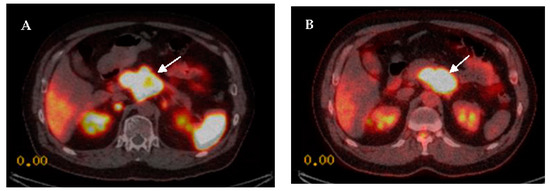

1.5. Diagnostic Value of Combined 68Ga SSTR and 18F-FDG PET in GEP-NENs

2. Dual PET Imaging Grading System

2.1. The NETPET Score

2.2. Three-Scale Grading System

- Karfis, I.; Marin, G.; Levillain, H.; Drisis, S.; Muteganya, R.; Critchi, G.; Taraji-Schiltz, L.; Guix, C.A.; Shaza, L.; Elbachiri, M.; et al. Prognostic value of a three-scale grading system based on combining molecular imaging with 68Ga-DOTATATE and 18F-FDG PET/CT in patients with metastatic gastroenteropancreatic neuroendocrine neoplasias. Oncotarget 2020, 11, 589–599. [Google Scholar] [CrossRef]